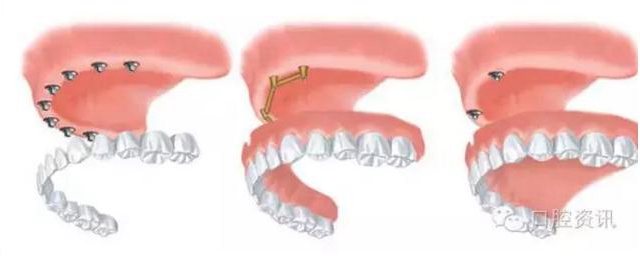

6.jpg

圖6. 全口牙齒缺失種植治療的各種選擇((1) 固定式(2) 桿卡式可摘義齒(3)球帽式可摘義齒)